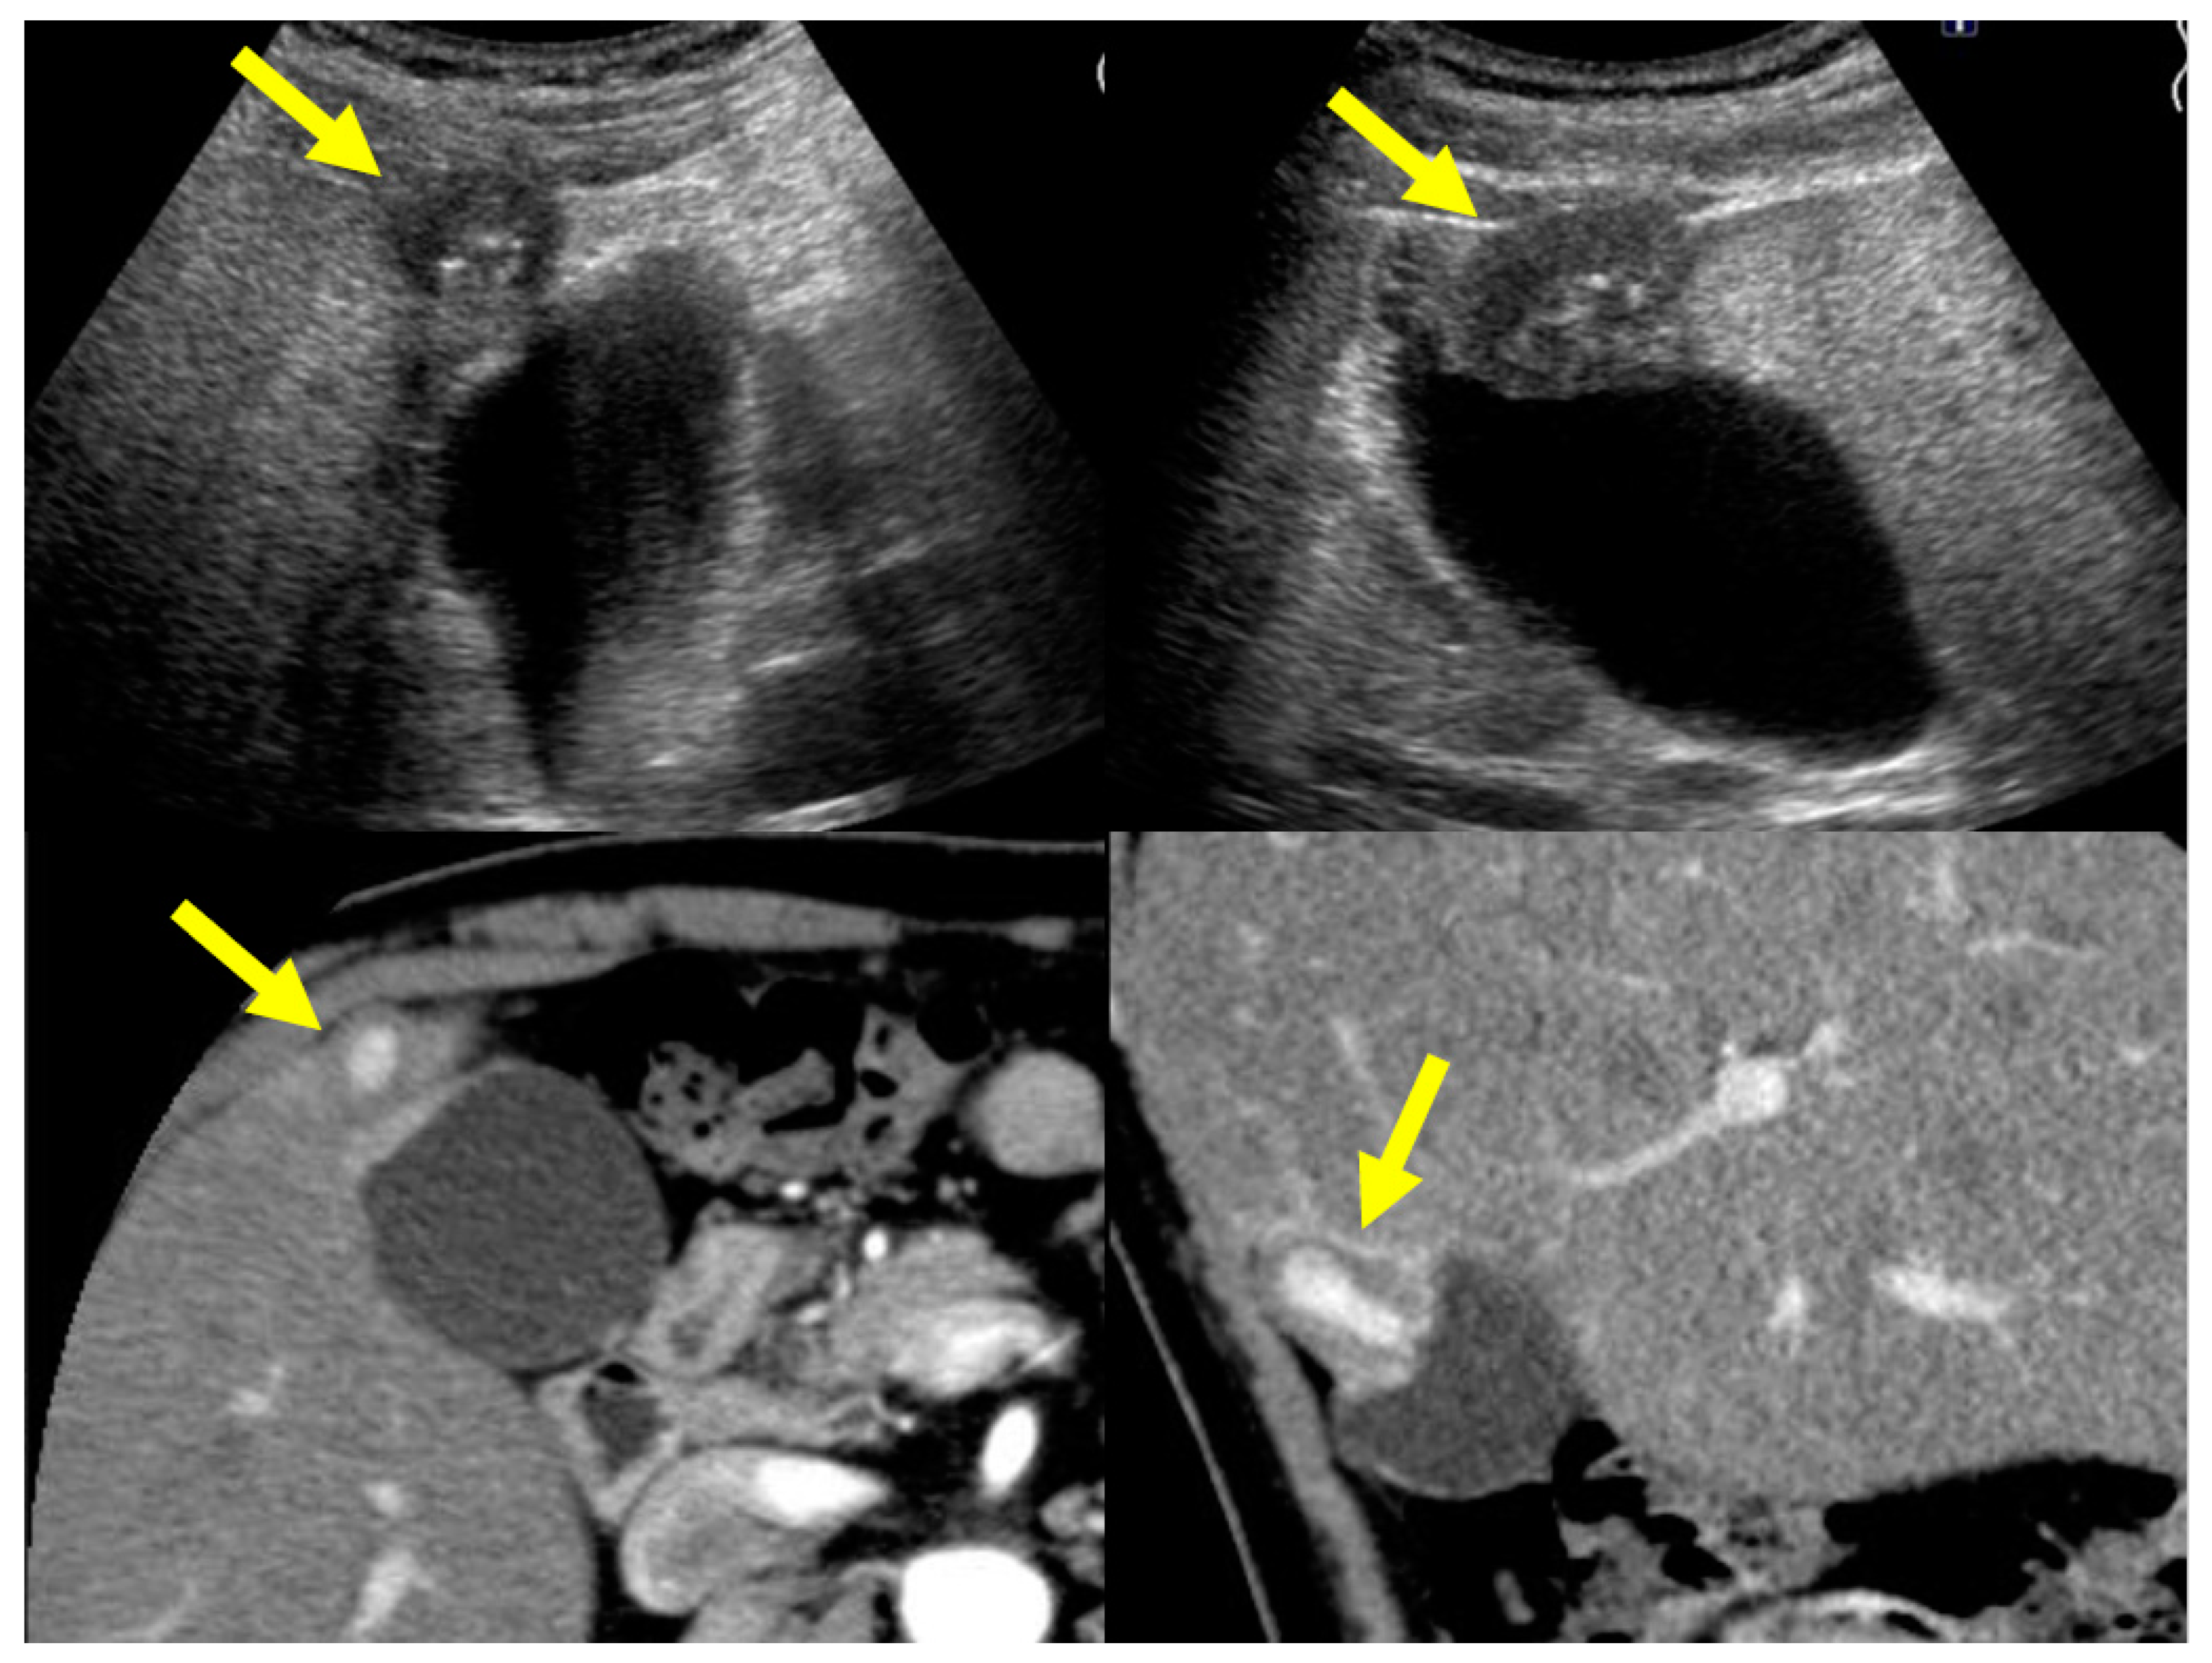

4.2. Localized Type of IgG4-CC

5.1. Gallbladder Cancer